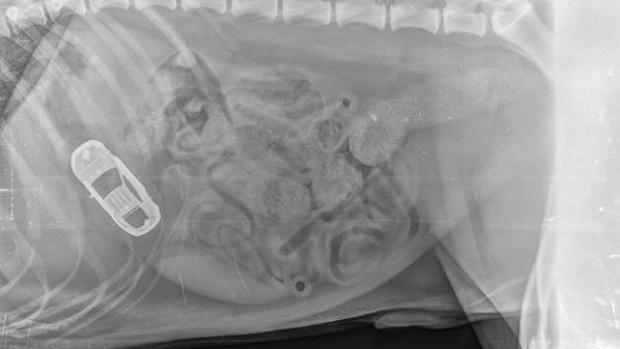

article-0-13F98B6C000005DC-514_634x486-xray-things-dogs-eat

dog-eat-homer-simpson-xray-things-dogs-eat